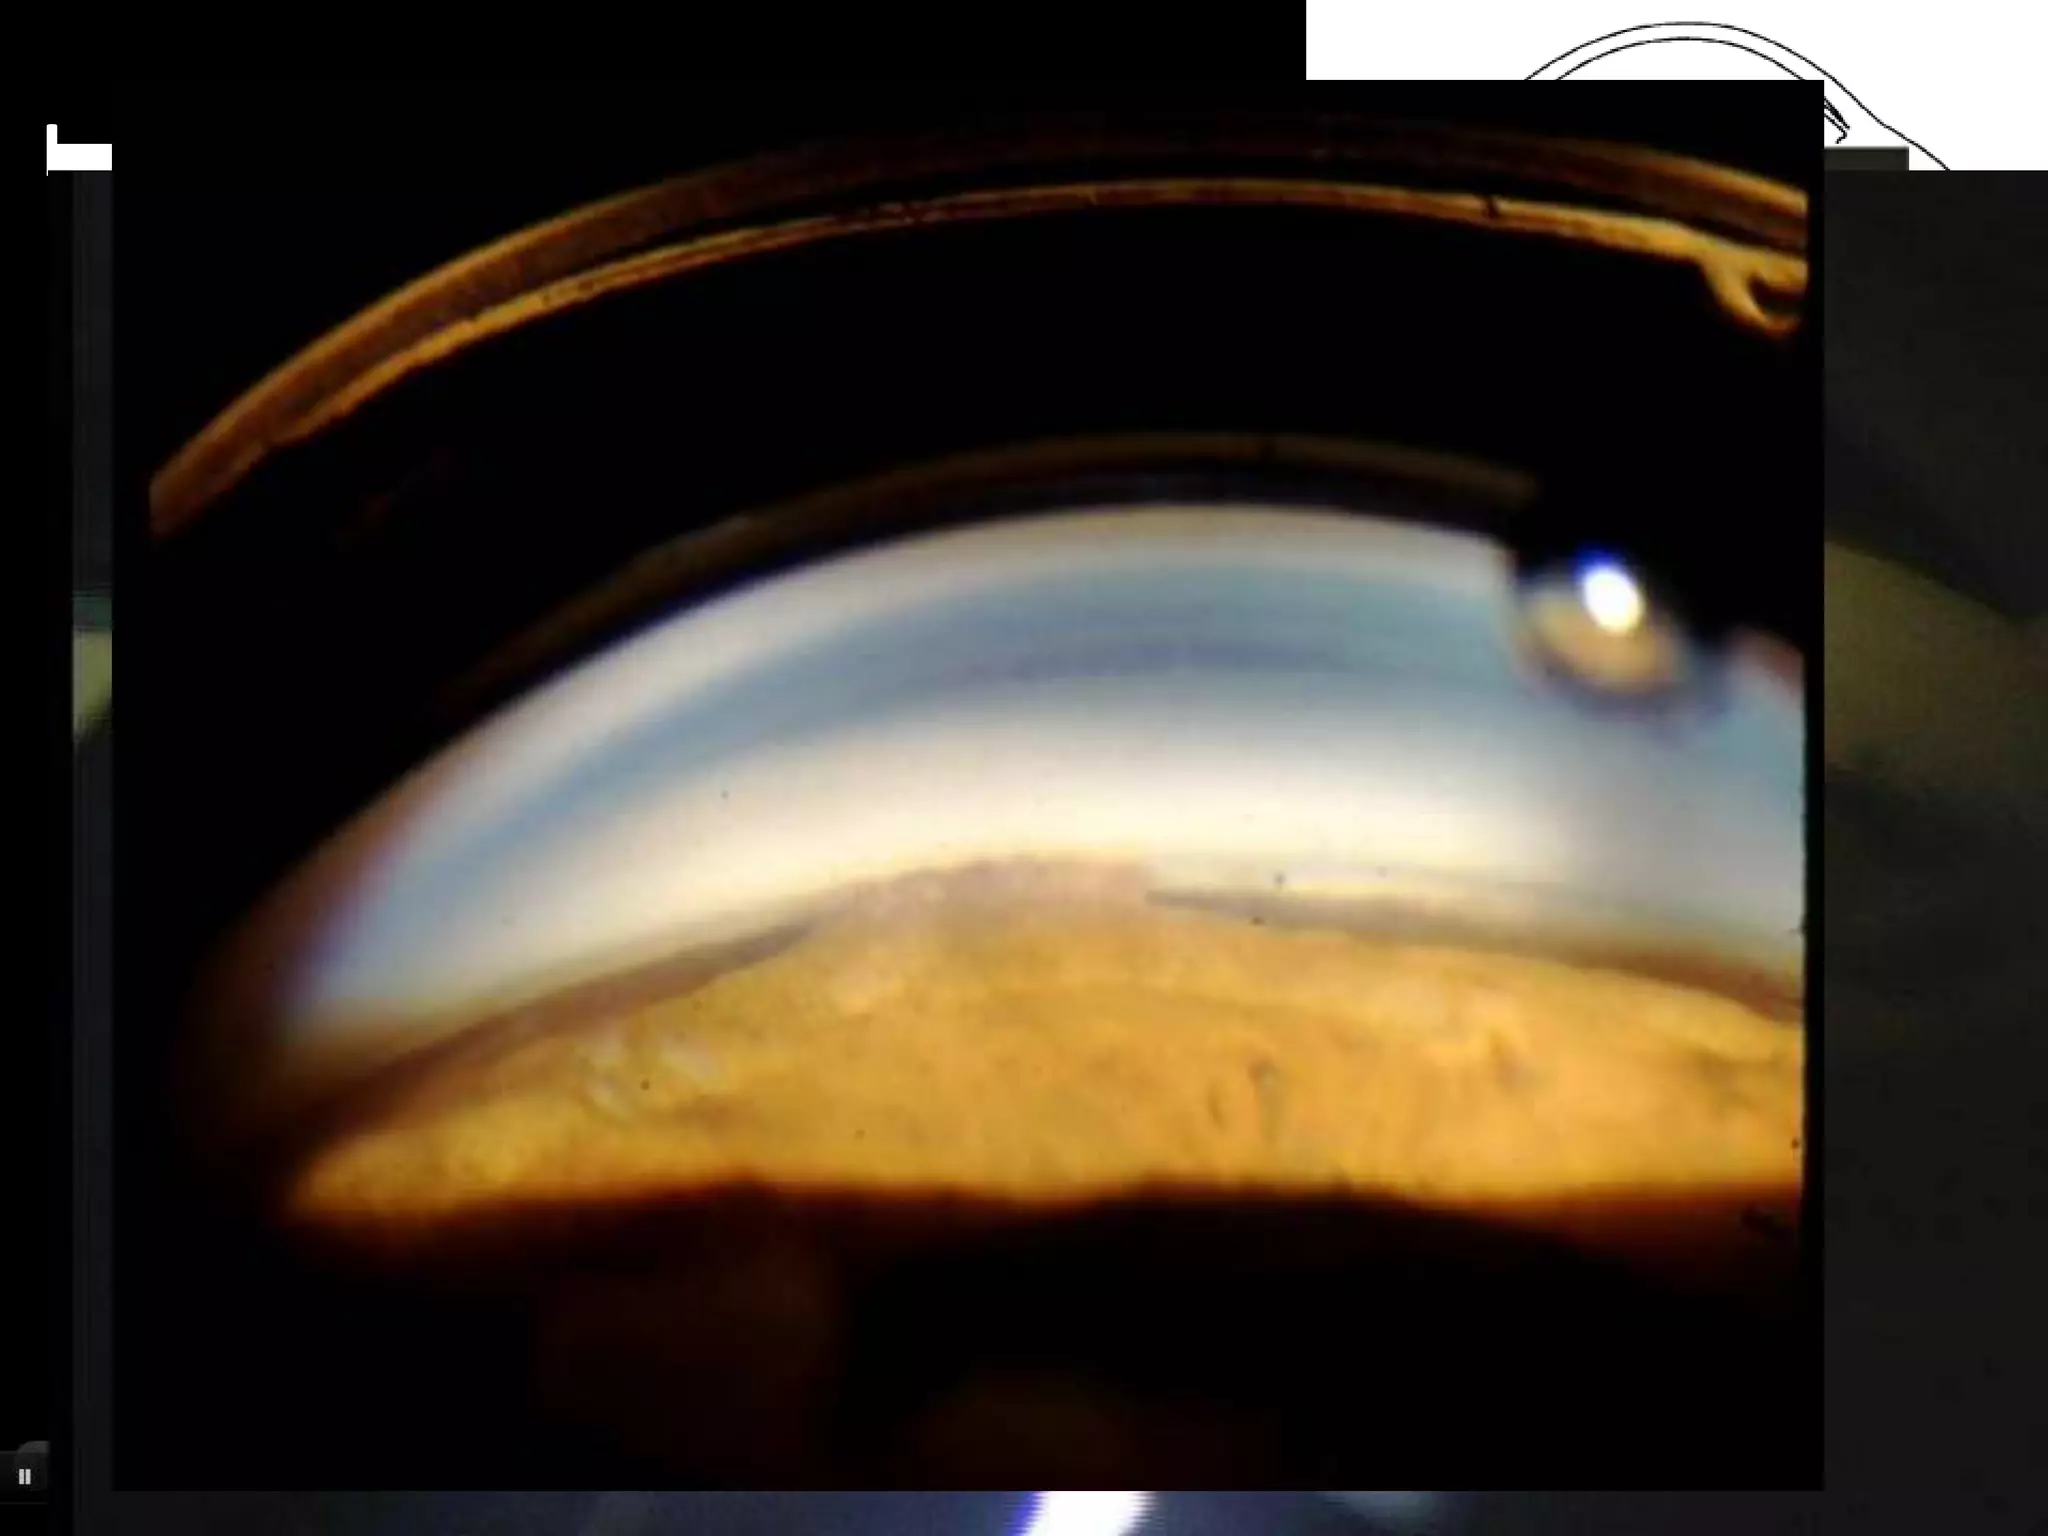

Indentation gonioscopy

• By changing amount of

pressure on cornea one

can observe effect on

angle width.

• Appositional vs PAS .

• Platue iris syndrom

• Phacomorphic glaucoma

Indentation gonioscopy •By changing amount of pressure on cornea one can observe effect on angle width. • Appositional vs PAS . • Platue iris syndrom • Phacomorphic glaucoma